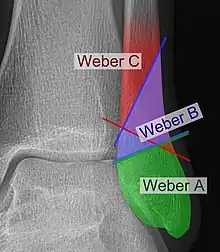

The Danis–Weber classification (often known just as the Weber classification) is a method of describing ankle fractures. It has three categories:[1]

- Type A

Fracture of the fibula distal to the syndesmosis (the connection between the distal ends of the tibia and fibula). Typical features:

- Type B

Fracture of the fibula at the level of the syndesmosis. Typical features:

- Type C

Fracture of the fibula proximal to the syndesmosis. Typical features: